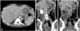

A gastroenterostomy is the surgical creation of a connection between the stomach and the jejunum. The operation can sometimes be performed at the same time as a partial gastrectomy (the removal of part of the stomach). [Source: Wikipedia ]